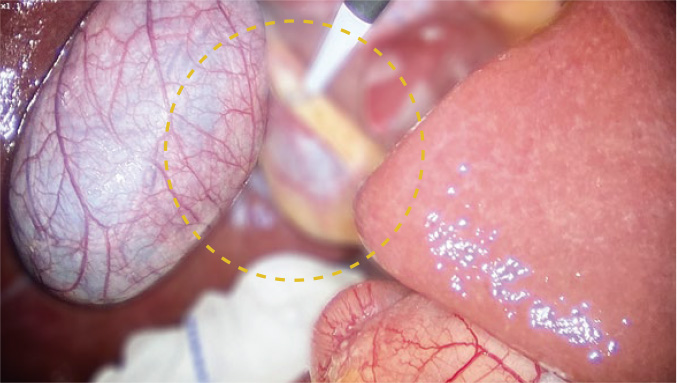

Accurately capture Near-infrared light, the white light andfluorescence image signals and processed separately to presentthe most precise and and purest fluorescence iamge.

Simultaneously displays white light, fused fluorescence and black-and-white fluorescence modes, with various modes freely switchable.